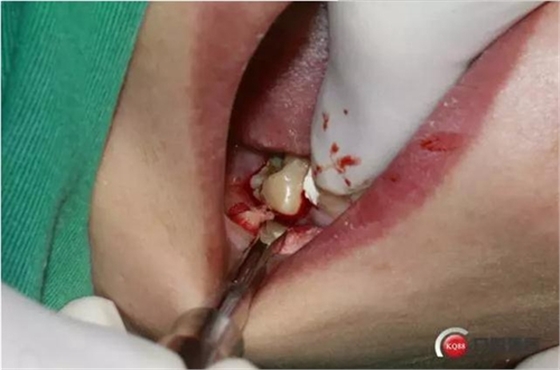

4%鹽酸阿替卡因腎上腺素局部麻醉,

口內(nèi)照片,48遠中三分之一覆蓋部分牙齦。